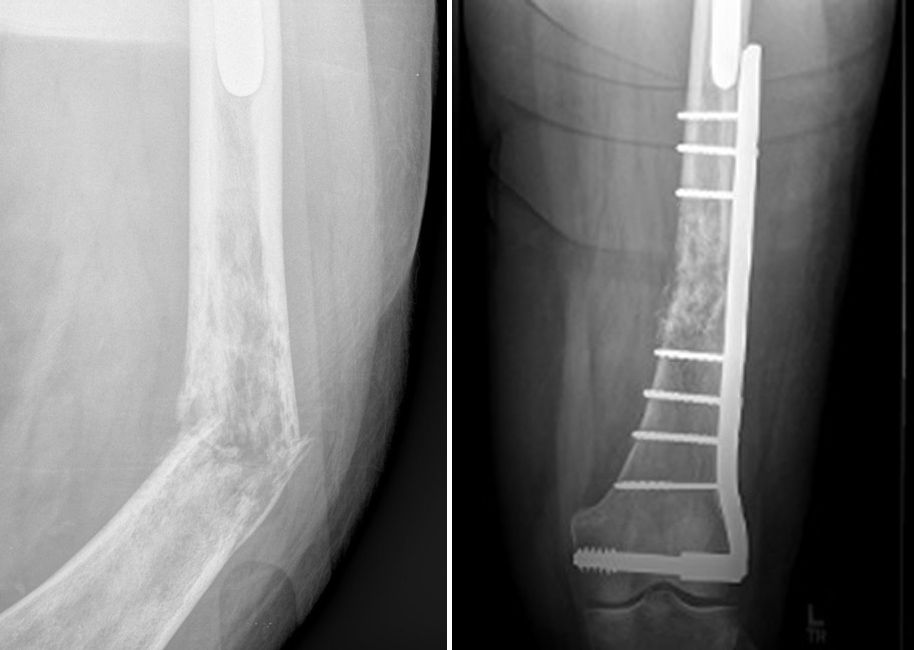

View Bone Lymphoma Xray US

View Bone Lymphoma Xray US.  simple to determine from plain. Patient with lymphoma demonstrating mediastinal widening due to adenopathy, splenic enlargement with displacement of stomach medially.

Non Hodgkin Lymphoma Of Bone Radiology Case Radiopaedia Org

Primary central nervous system (cns) lymphoma treatment options include radiation, chemotherapy, targeted therapy, and corticosteroids. Lymphoma is a blood cancer that starts in the body's immune system cells. Primary bone (skeletal/osseous) lymphoma (pbl) is a less common manifestation of lymphoma than secondary involvement from disseminated lymphoma.